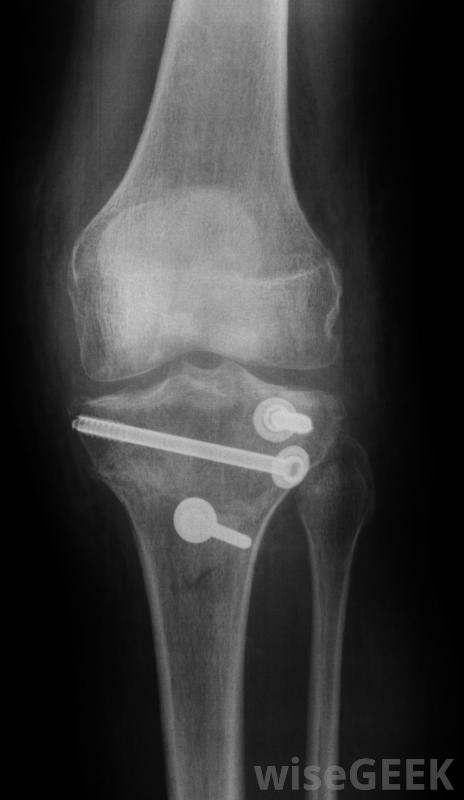

骨钻可以帮助挽救原本需要截肢的四肢当把一个销钉安装到骨头上时,外科医生可能需要铰出一个孔,以便正确地安装销钉。骨钻能够轻松地完成这个功能。用更原始的手动工具可能需要几个小时才能完成,而完成这项工作所节省的时间就是时间病人不需要麻醉,这往往是影响危重病人存活率的一个因素严重骨折,外科医生能够挽救许多需要截肢的肢体。骨钻通常是电力驱动的。马达以惊人的速度运转,使钻穿硬骨看起来很容易,这种手术并不仅仅局限于骨折的修复骨髓钻也用于从骨髓中提取骨髓。骨髓是通过在骨头上钻一个小孔取出的。在很多情况下,通过身体的再生能力,这个洞会逐渐被新的骨头填满。

骨钻会制造出钉和螺丝固定的孔与手动钻相比,电动骨钻有两个好处。手钻钻钻骨需要更长的时间,这意味着患者失去意识的时间更长。而且,手钻没有那么精确。当外科医生转动钻头时,钻头会摇晃移动。这导致了一个长方形的孔。电钻以快速而精确的方式通过,在骨头上形成一个精确大小的孔

金属板和螺钉可用于固定横向骨折,使用骨钻。孔的精确公差允许螺钉和销更好地配合,同时促进更快的愈合。由于钢板和螺钉的更好配合,骨能够更好地自我修复,并且通常与骨折前一样牢固或更牢固。其操作机构是密封的,因此能够轻松消毒。这减少了感染的机会,并保护钻头免受任何外部污染